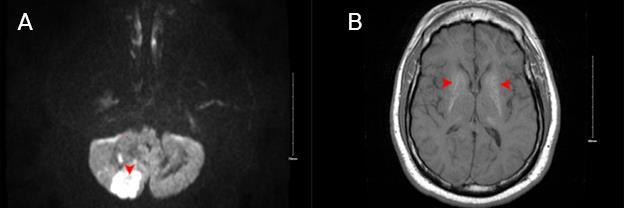

349 Acute Cerebellar Infarct in A Patient with Undiagnosed Fahr’s Syndrome: A Case Report

RW Slaven, M Huecker, D Kersting

357 Wernicke Encephalopathy Associated with Hyperemesis Gravidarum: A Case Report

B Kreutzer, B Buehrer, P Rohde, A Pelikan